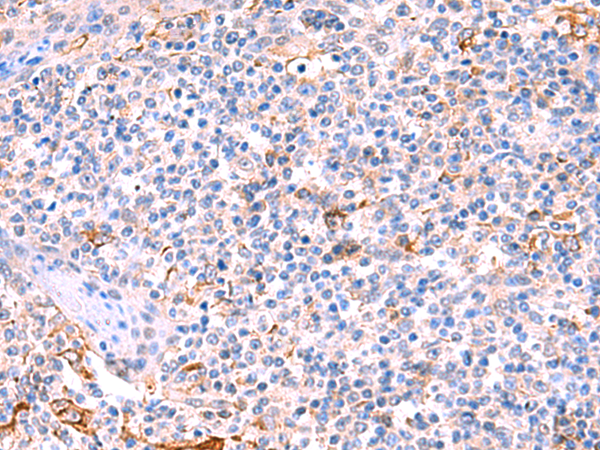

IHC positive control:

Human tonsil and Human cervical cancer

IHC Recommend dilution:

50-300